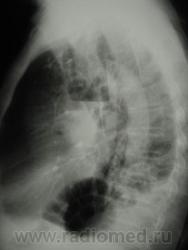

Да, вроде бы и легкое уменьшено, и средостение уехало. А что там за огромный абсцесс? Не опухоль же распадается? Такого с уровнем не должно быть.

случай давнишний, у пациента подтвержденный центральный рак, оперировать не стали, пришел когда хуже почувствовал себя, я ему тоже написала абсцесс. а куда он делся дальше незнаю((((((

И не просто абсцесс, возможно, еще и с задне-базальным осумкованным выпотом.

Несколько иллюстраций к вышесказанному.